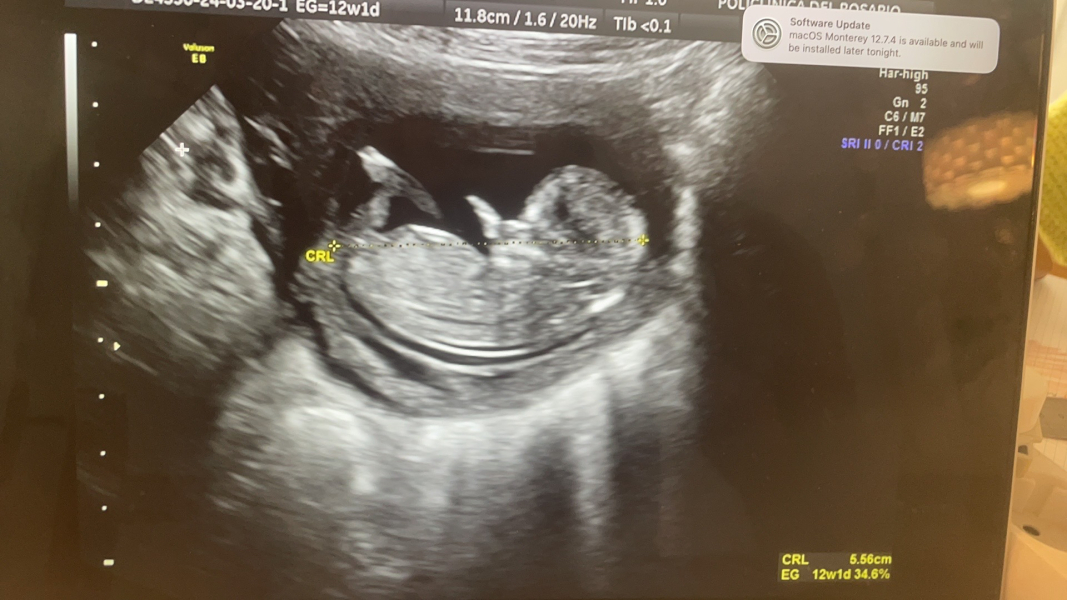

I had my 12 week scan today....... what do you think- boy or girl??!!

@CharlotteB94 what a lovely scan pic!

Lovely scan pictures @CharlotteB94 @yellowrosee! ❤

@yellowrosee wow look at that! Smile

so lovely seeing your scan! 🥰